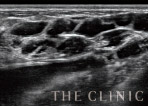

- しこりを訴えたゲストのエコー画像

アクアフィリングの注入後わずか半年で、しこりとバストの変形を訴えて来院されたゲスト。

エコー検査を行ったところ、アクアフィリングの塊が確認されました。アクアフィリングは3~5年は効果が持続すると言われていただけに、かなりショックだったことでしょう。